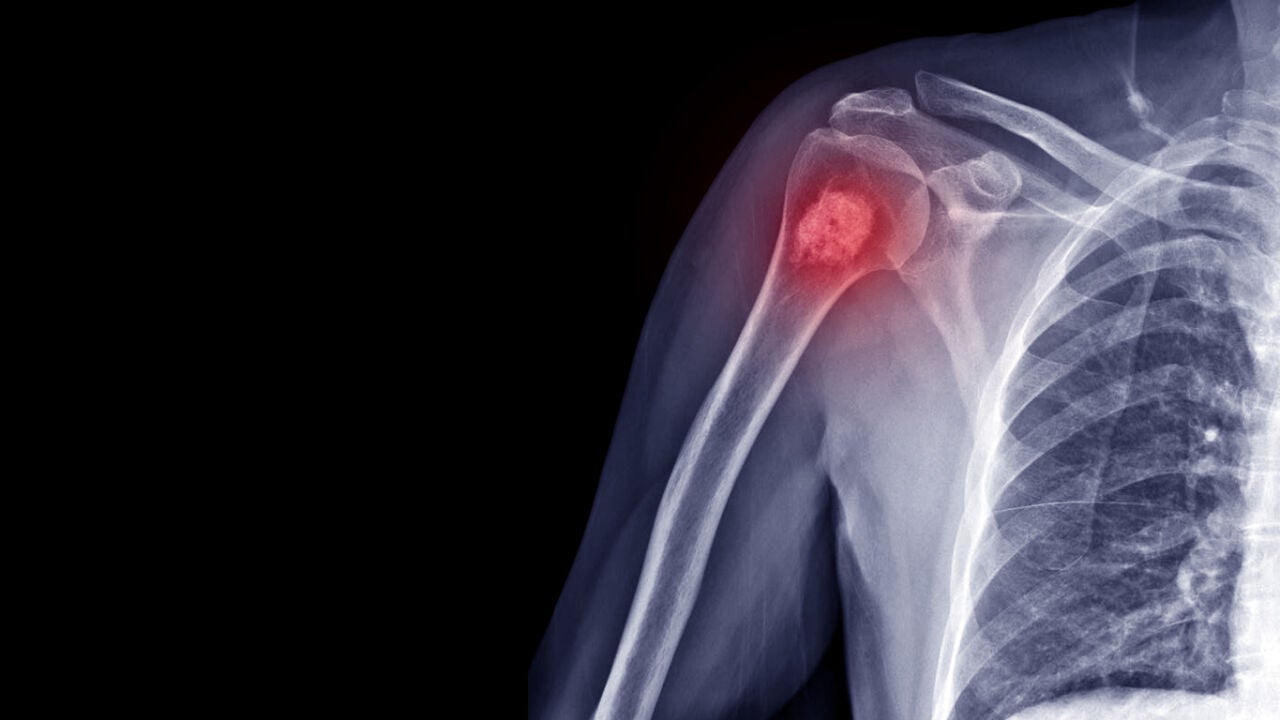

Cáncer de huesosiStock

Es poco habitual que un cáncer comience en el hueso. Lo más normal es que llegue hasta allí a través de una metástasis procedente de otro tumor. Este tipo de cáncer puede aparecer en cualquier hueso, pero suele afectar al fémur.

Existen tres tipos de cáncer de hueso: el osteosarcoma, el condrosarcoma y el sarcoma de Ewing. Tal y como explican en Mayo Clinic, el primero es un tipo de cáncer de hueso que comienza en las células que forman los huesos. Es el tipo más común de cáncer de hueso. Suele aparecer con más frecuencia en adolescentes y jóvenes adultos, pero también puede aparecer en niños y adultos mayores.

El condrosarcoma es un tipo de cáncer que, por lo general, comienza en los huesos, pero a veces puede presentarse en el tejido blando. El condrosarcoma es más frecuente en la pelvis, la cadera y el hombro. Con mayor frecuencia, aparece en adultos de mediana edad y adultos mayores.

Por último, el sarcoma de Ewing es un tipo de cáncer de hueso que aparece en los huesos y en el tejido blando que los rodea. Se presenta más a menudo en niños y adultos jóvenes, aunque puede aparecer a cualquier edad.